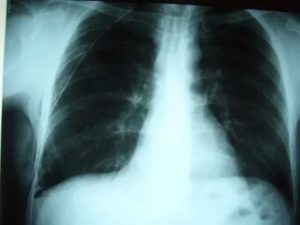

- Рентген. Проводится рентгенография в нескольких проекциях. Метод позволяет определить область поражения и характер процесса. На снимках патология проявляется затемнениями с размытыми контурами (на фото).

Плеврит легких на рентгенограмме